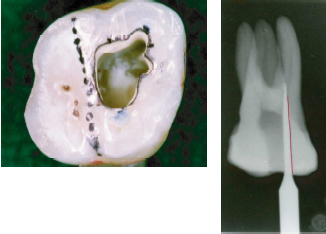

![]() MHアクセスバーNo.1による根管上部形成前 |

![]() MHアクセスバーNo.1による根管上部形成後